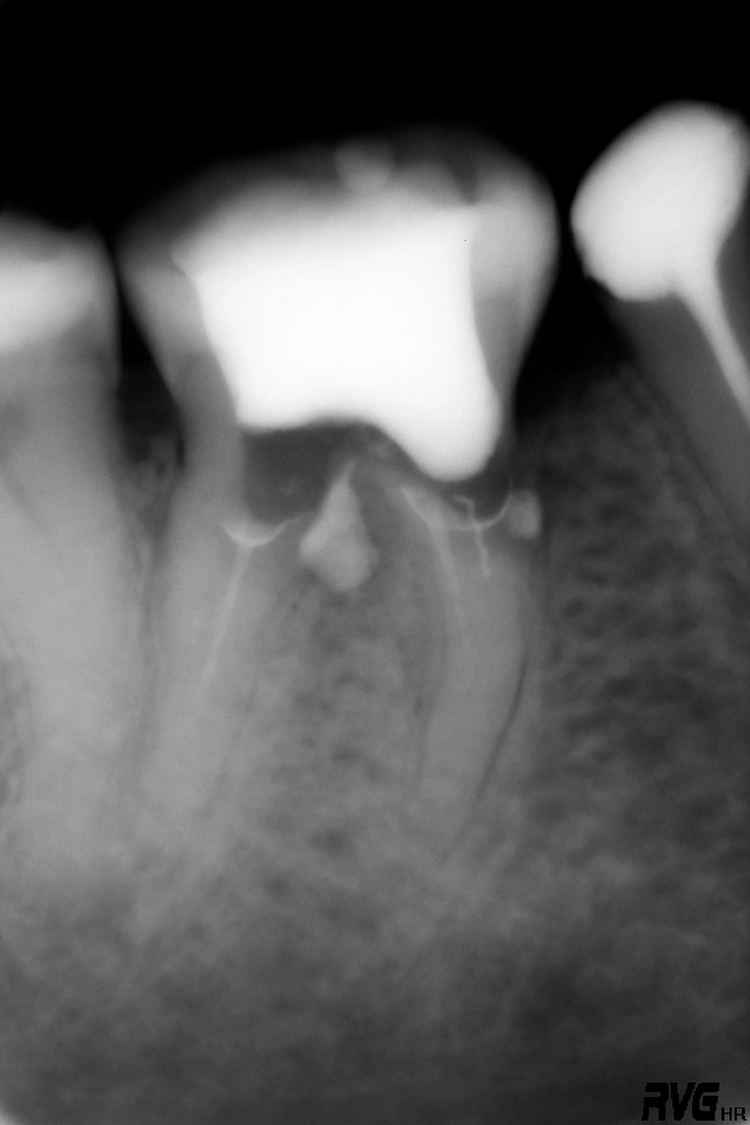

Die Schwierigkeit der mechanischen Ausformung eines Wurzelkanals steigt mit zunehmendem Krümmungswinkel und abnehmendem Krümmungsradius an (Abb. 1). Eine koronale Lokalisierung der Krümmung erhöht die Wahrscheinlichkeit einer Instrumentenfraktur im Vergleich zu einer Krümmung des Wurzelkanals im mittleren oder apikalen Wurzeldrittel [2] (Abb. 2).

Deutlicher zeitlicher Mehraufwand liegt häufig in prozessualen Fehlern, wie bspw. übermäßigem Zahnhartsubstanzabtrag, begründet. Dieser kann zu Kanalverlagerungen und -perforationen führen (Abb. 3a und b), die ein erhöhtes Risiko für anschließende Wurzellängsfrakturen sowie den Verlust des Zahnes darstellen können [12].